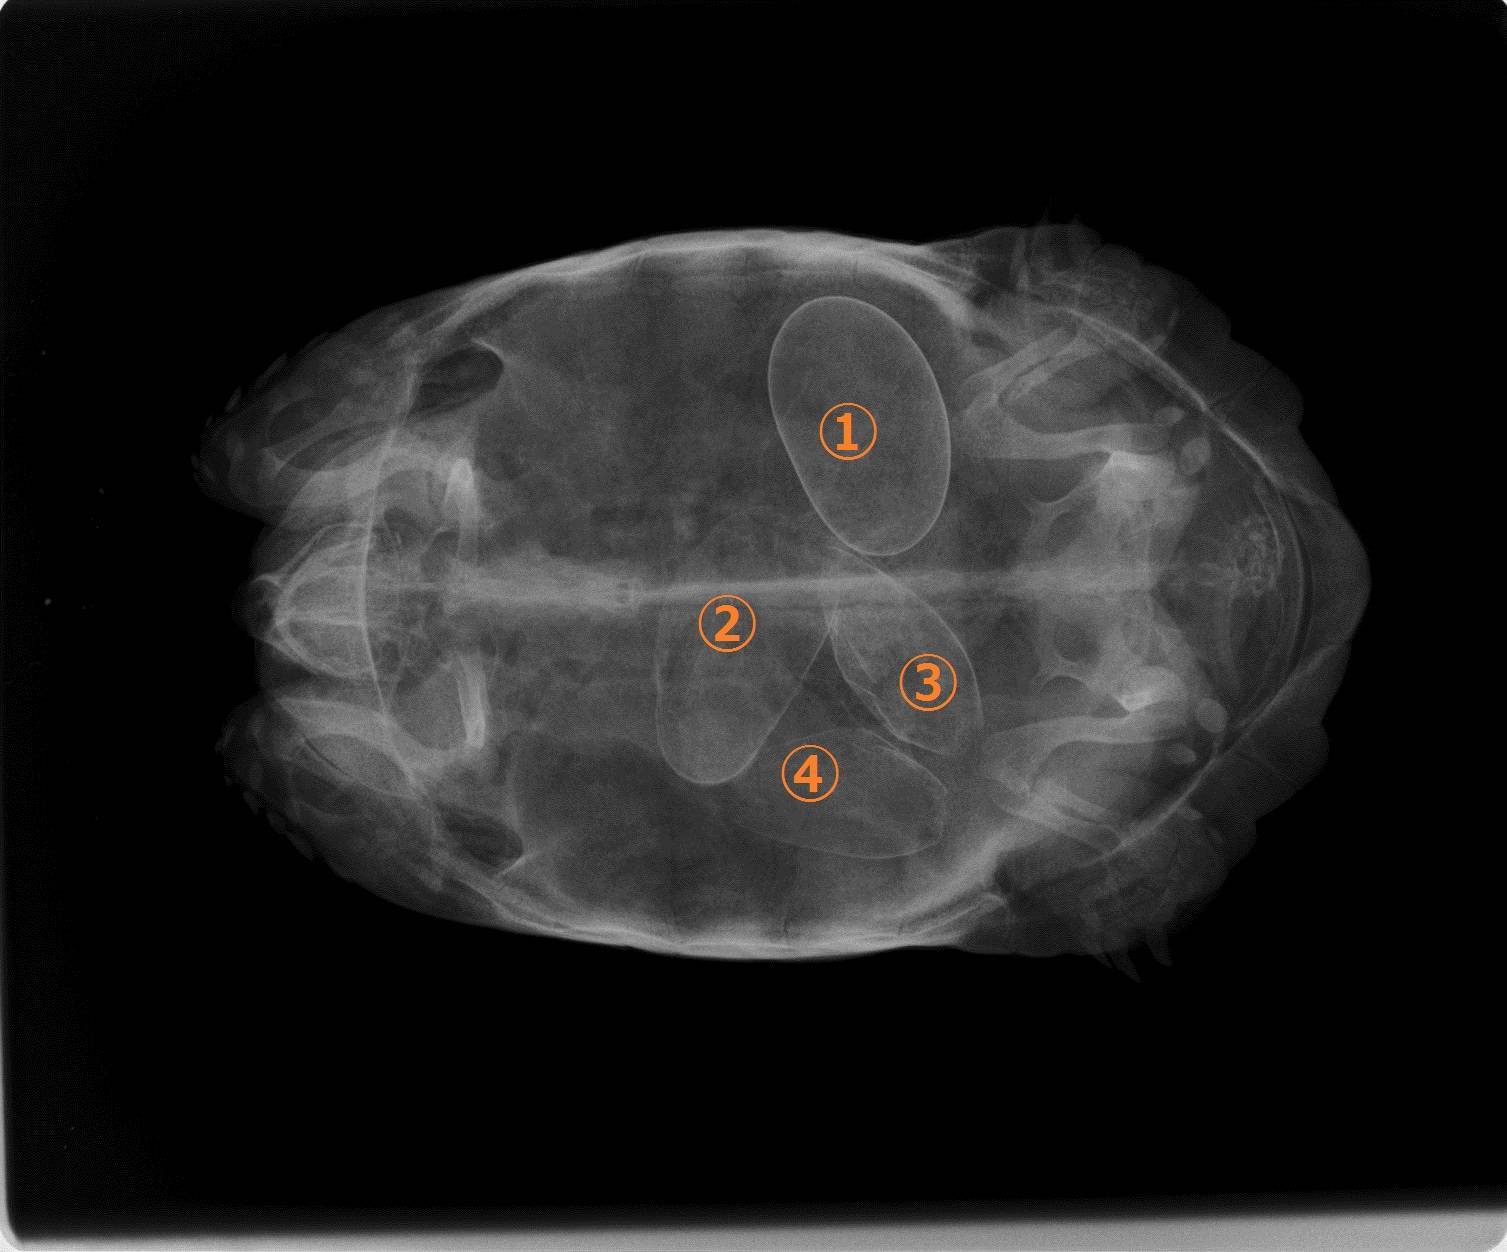

なぜ卵があるのがわかったかというと、レントゲンを撮ったからです。

このように4個の卵が確認できました。

形のいい1個(①)は注射をして産ませることができたのですが、残りのいびつな3個はちっとも動きません。